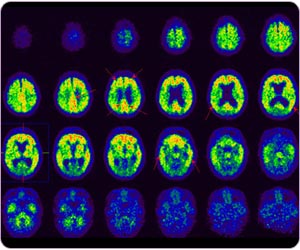

11C 标记PIB 正电子扫描脑部:病人在post cingulate gyrus, frontal lobe, precunes, parietal lobe, temporal lobe区域都呈现淀粉斑块,诊断为阿耳滋海默氏病。

阿耳滋海默氏病 (11C标记PIB正电子扫描脑部)